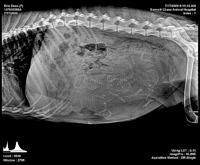

Calla Flicker pups 5 wks old 710